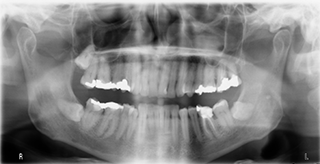

OPG

Gives a complete image of all the teeth and jaw bones.

Hence facilitates better diagnosis.